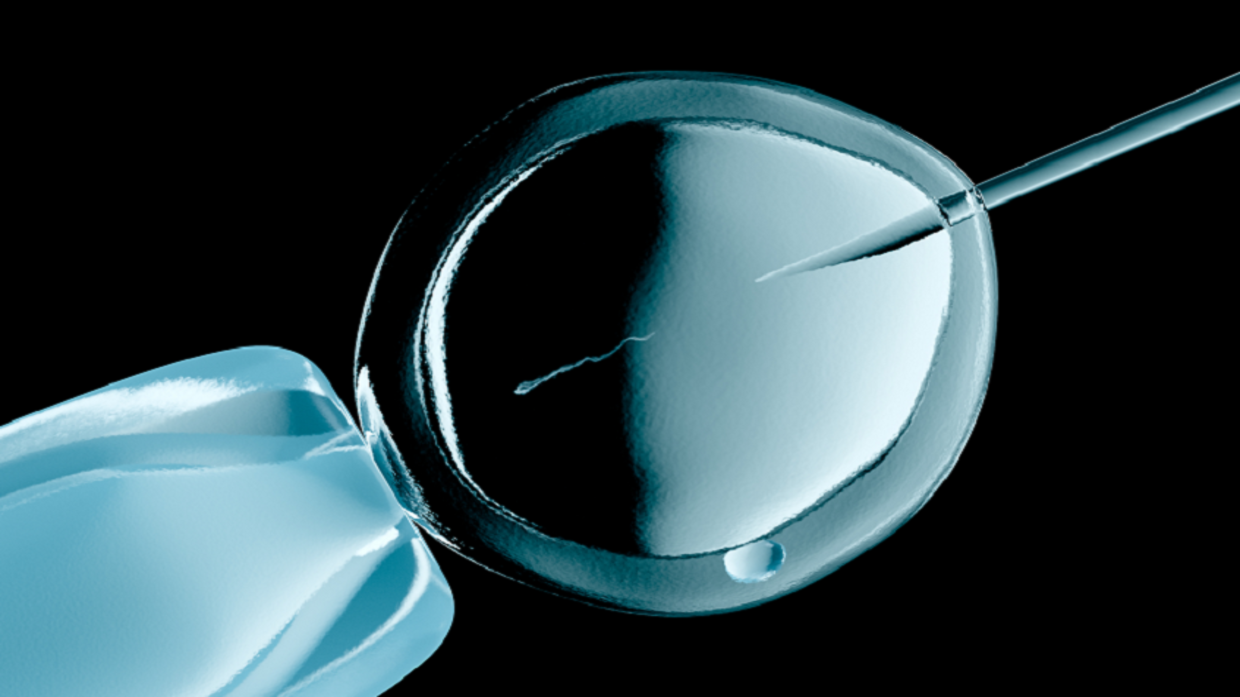

التلقيح الصناعي – صحة وحياة

تتطلب الممارسات السريرية الحالية لتقييم مورفولوجيا (علم التشكّل) الحيوانات المنوية، تحليلا بشريا

وتلوينا كيميائيا لخلايا الحيوانات المنوية، ما قد يسبب الضرر.

مضيفة: “في بعض الأحيان، يحتاج علماء الأجنة في التلقيح الصناعي إلى حقن حيوان منوي واحد مباشرة في البويضة لزيادة فرص الإخصاب.

وفي حين أنهم خبراء في العثور على أفضل حيوان منوي لهذه العملية (الحيوان المنوي بالشكل والحجم المناسبين ويتحرك بحرية)، فقد يستغرق الأمر أحيانا ساعات لفحص العينة والعثور على أفضل حيوان منوي للحقن”.